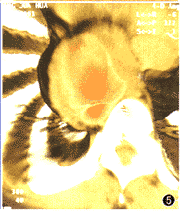

主动脉假性动脉瘤3例。CTVE表现为动脉管壁于某处突然中断,在中断处有一裂隙与周围一不规则形大腔相通,同时仍可看到正常的动脉管腔(图4~6)。

图4~6 主动脉假性动脉瘤。图4为多平面重建法(MPR)图像,示胸主动脉假性动脉瘤。图5为CTVE图像,示正常降主动脉、裂口、假腔。图6为CTVE图像,示腹主动脉假性动脉瘤裂

3.主动脉假性动脉瘤:可发现动脉壁破裂的位置、裂口形态及长度等, 这是现有的其他检查手段所无法做到的。本组病例中,3例假性动脉瘤均发现了破口位置,为临床提供了强有力的依据。值得一提的是,为我院1例高难度腔内隔绝术治疗巨大腹腔干假性动脉瘤的手术提供了极有价值的信息,保证了手术的成功,是其他检查手段无法取代的。